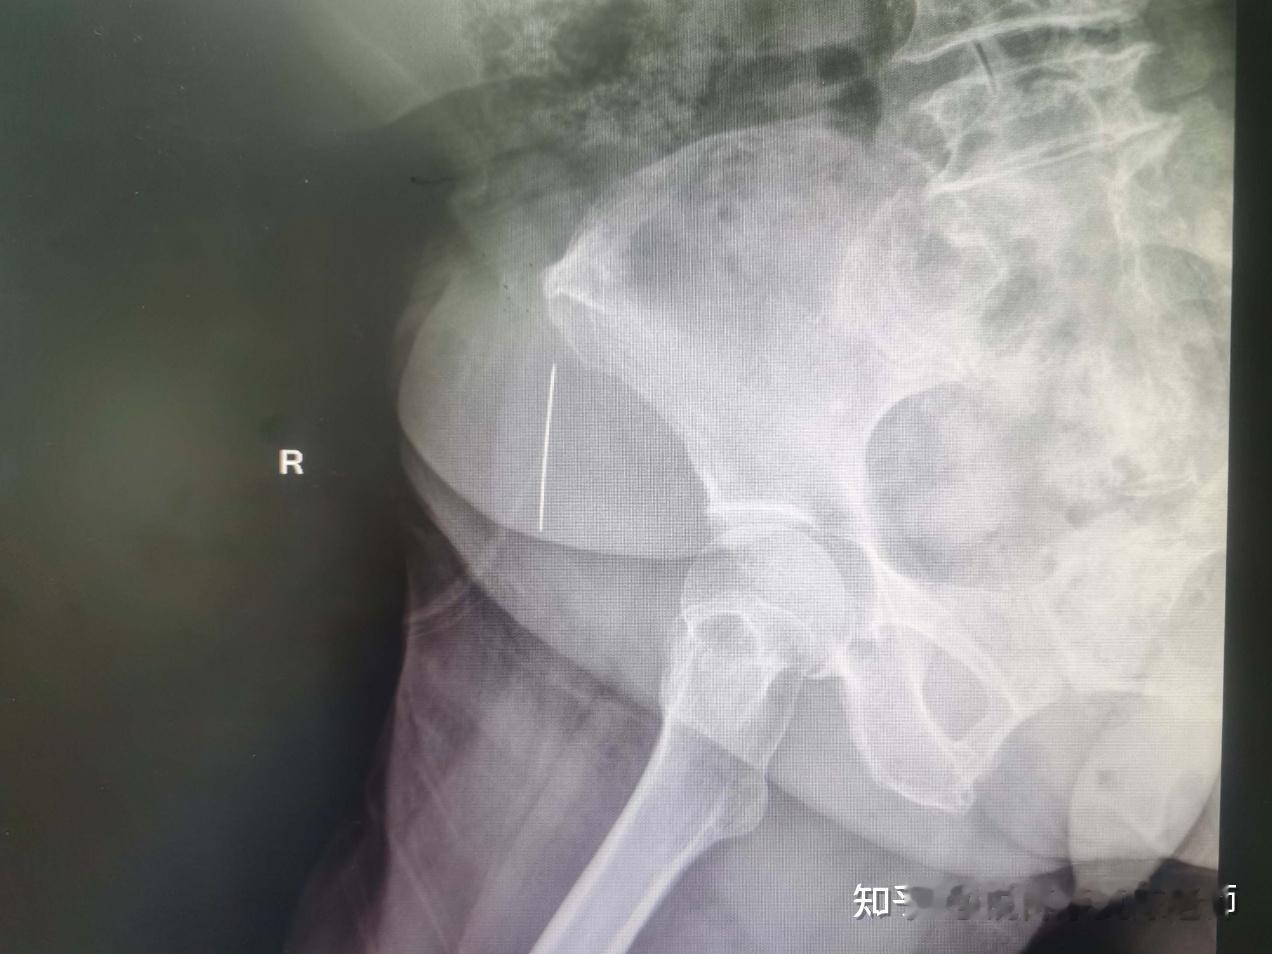

“太吓人了!”近日,广东广州,一34岁男子得了感冒,就想着用高温汗蒸排排毒,两天内做了三次。可没想到,第三次做完后,竟然直接晕倒了,去医院也没检查出个所以然来。后来去了脑科医院,结果竟是血栓引发的脑梗!网友:水被蒸干了! 据媒体4月16日报道,该男子平时经常熬夜,上班也是久坐,抵抗力逐渐变差了。前段时间,他发现自己开始流鼻涕,还发起了低烧。他觉得自己是感冒了,就想着做个汗蒸,好好排排毒。 短短两天时间里,他做了三回,每次都是一个多小时,最为重要的是,这一个小时里面,他一口水都不喝,整个过程只出不进。第三次汗蒸做完之后,就直接晕倒在了外面。 等他被送到医院后,却并没有查出什么异常。可是他却发现,自己的精神一天不如一天,走水都晃荡,站着还想睡觉。他又去了三九脑科医院。这次的磁共振显示,他的颅内血管有多处血栓,导致了脑梗死。 男子的血栓就是汗蒸引起的。汗蒸本身没有问题,但是过程中得注意补水,只蒸不补,脑内就会缺水,很容易形成血栓。 网友看后表示,做汗蒸前,应该会有给科普吧,觉得渴了就要及时补水。这也是个常识吧!估计他当时光想着蒸蒸把感冒赶走了! 信息来源:《34岁男子两天汗蒸三次 脑子“缺水”诱发血栓 医生:大量出汗后应及时补足水分》广州日报